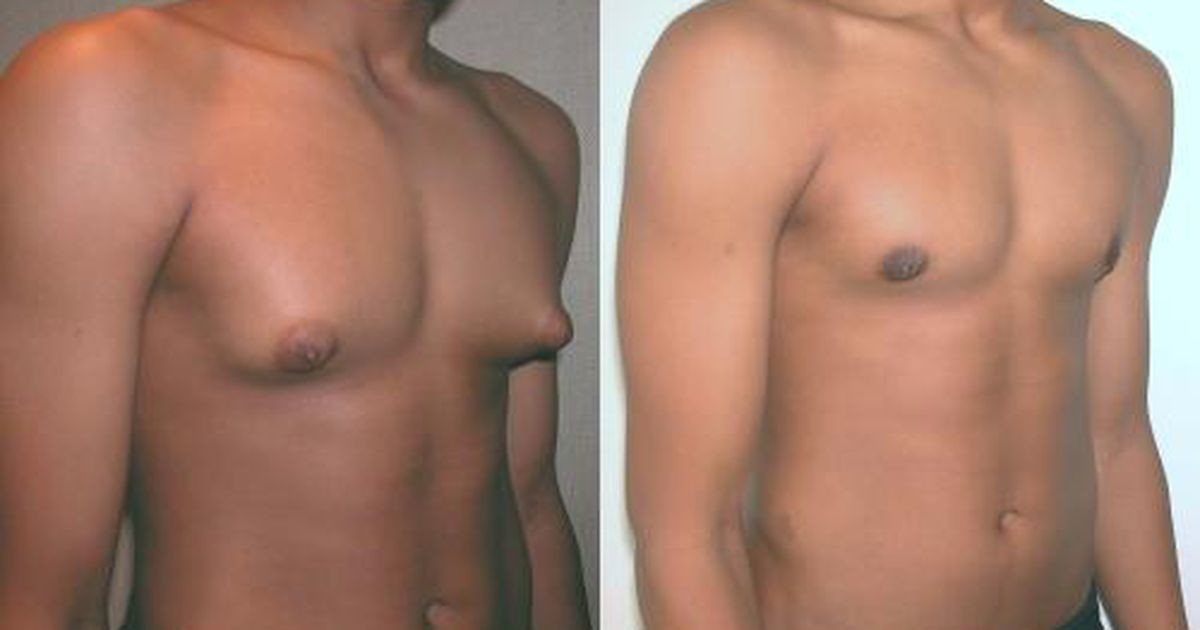

Гинекомастия

Проявляется увеличением грудных желез у мужчин вследствие разрастания жировой или железистой ткани. Причиной возникновения гинекомастии является изменения гормонального фона, который протекает с преобладанием женских половых гормонов над мужскими в организме мужчины. Кроме природных гормональных изменений в период полового созревания, факторами, способствующими возникновению патологии могут быть:

Симптомы гинекомастии

- визуальное увеличение грудной железы

- боль и чувство напряжения в грудных железах

- изменение цвета кожного покрова

- выделения из соска

Диагностика гинекомастии

- обследование грудных желез, половых органов и периферических лимфатических узлов

- обследование щитовидной железы

- лабораторные исследования — анализ крови, определение показателей функции печени и почек, общий тестостерон, онкомаркеры при подозрении на злокачественную опухоль

- УЗИ обеих молочных желез и яичек

- КТ или МРТ

- биопсия молочной железы — при подозрении на рак

Гинекомастия лечится хирургически. Во время оперативного вмешательства удаляется избыточная ткань, методом липосакции удаляется жировая ткань. Для восстановления нормального вида молочной железы применяется пластическая хирургия (маммопластика), что позволяет сохранить внешний вид груди и лишает пациента психологического дискомфорта.

Во время оперативного вмешательства удаляется избыточная ткань, методом липосакции удаляется жировая ткань. Для восстановления нормального вида молочной железы применяется пластическая хирургия (маммопластика), что позволяет сохранить внешний вид груди и лишает пациента психологического дискомфорта.